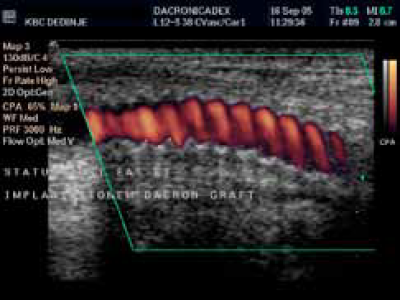

Duplex-ultrasonografski

nalazi postoperativno:

(a) By pass graft od impregniranog Dacron-a.

Karotidna restenoza se nekad mora korigovati interpozicijom by pass grafta (Dacron).

Rekonstrukcija bifurkacije sa dakronskim graftom zbog restenoze.

Uredan nalaz Spektralna analiza